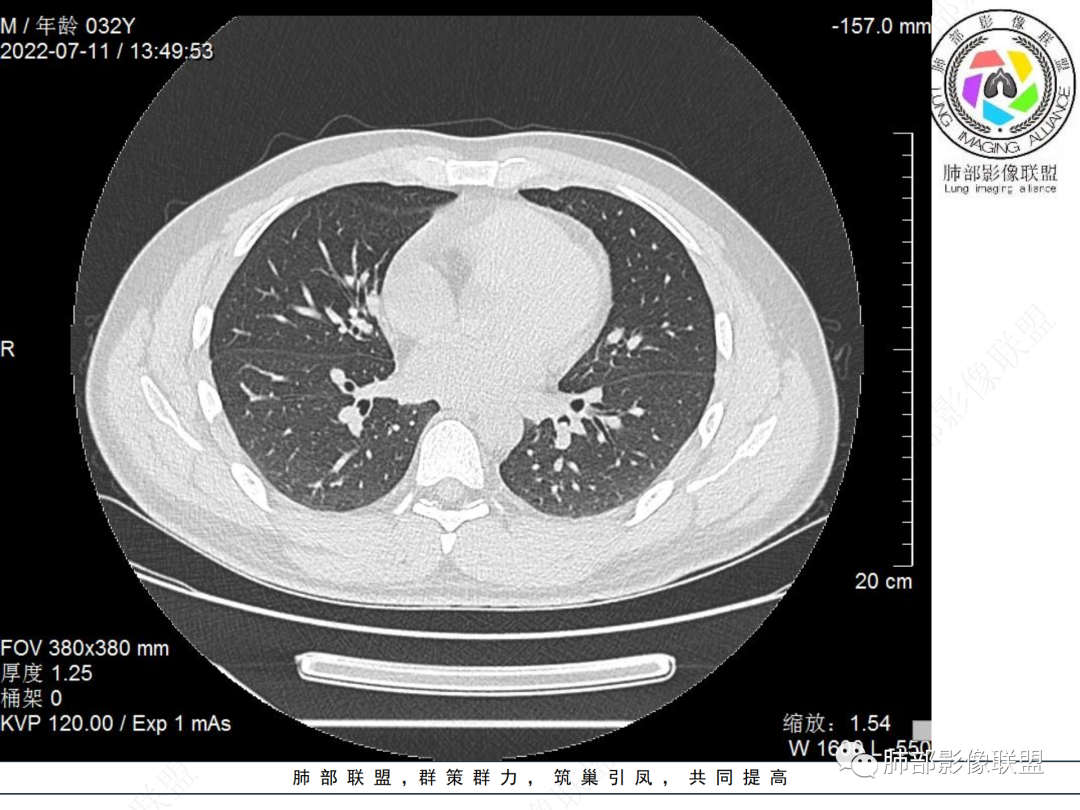

左肺下叶后基底段开口处结节,边缘光滑清楚,没有增强扫描,年轻男性患者痰血三天,考虑1.良性病变:腺瘤、错构瘤、平滑肌瘤

2.恶性:类癌、粘液表皮样癌。

左肺下叶外后基底段气管内见结节状影,边缘部分清晰。考虑错构瘤,待排恶性病变。

左肺下叶气管内外占位病变,咯血病史,考虑类癌,粘表待排。

青年男性,左肺下叶后基底段支气管开口软组织结节,边缘光整,气管镜提示质软,易出血,考虑类癌

左肺下叶气道腔内占位,远端无花花草草,疾病谱:鳞,类癌,粘表,腺样囊腺癌,小,无增强,不好判断,临床咯血,选类癌。

左肺下叶后基底段开口处结节影,边缘光滑,患者年龄较小,首选类癌

男性,咳血左肺下叶支气管腔内结节影,没有阻塞性炎症,考虑类癌,鳞癌

左肺下叶后基底段开口处腔内见壁结节,花生米样,宽基底,补充增强及矢状位重建,确定我无向壁外突破浸润生长,另见强化的特点,临床触之易出血,类Ca可能性大。

年轻男性,咳血,左肺下叶后基底段支气管腔内结节,边缘光滑,首先考虑青年三件套,类癌大于粘液表皮样癌,支气管镜质软,触之易出血,鉴别血管瘤,平滑肌瘤

左肺下叶后基底段开口部结节,密度较均匀一致,边缘较光整,目测密度偏低,支气管镜示:质软、触之易出血,考虑恶性,类癌。

青年男性,左肺下叶后基底段支气管开口软组织结节,边缘光整,气管镜提示质软,易出血,考虑恶性类癌

左肺下叶后基底段开口处结节影,边缘光整,年轻患者,伴咯血,考虑鳞癌,类癌不能排除